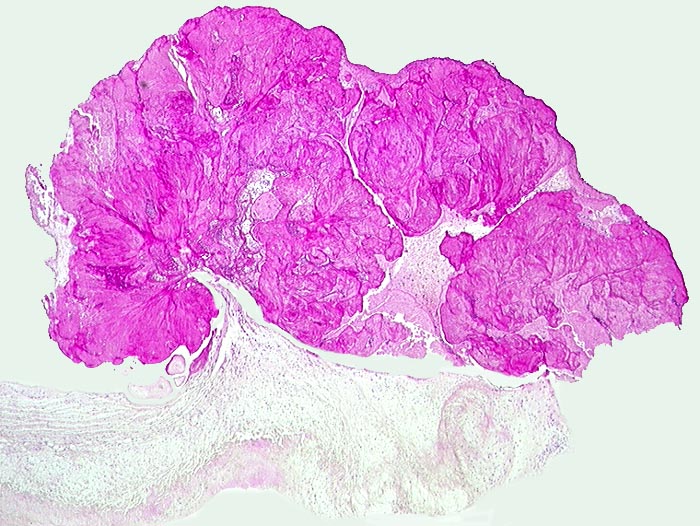

PathoPic ID 135 - Endocarditis marantica

Endocarditis marantica

Entzündung / Reparatur

Aortenklappe

Kardiovaskuläres System

Der Aortenklappe ist eine Vegetation aus Fibrin aufgelagert.

Metastasierendes Bronchuskarzinom.

Histologie